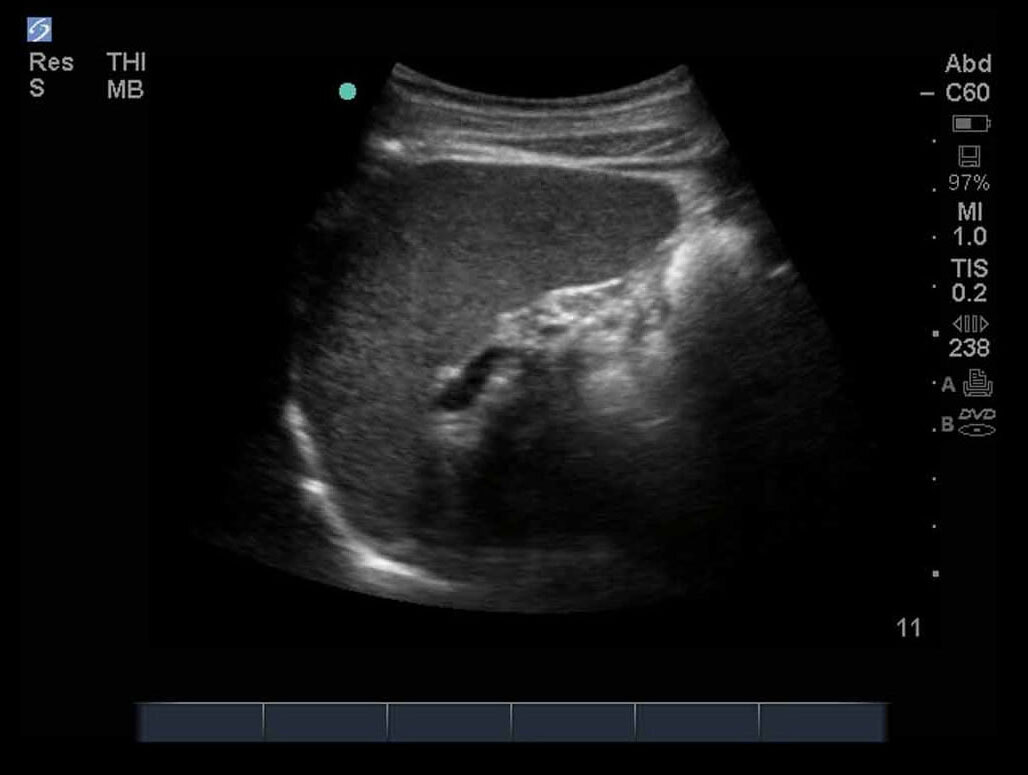

FAST Left Upper Quadrant (LUQ) 3 Image

M-Turbo: FAST Exam, Left Upper Quadrant 3.